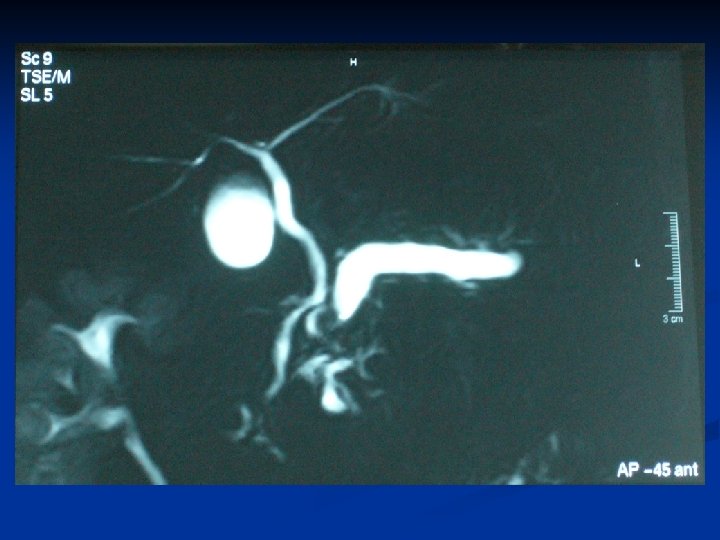

n n n CASO 1. PAC M. V. ICTERICIA EN ESTUDIO Paciente. Visitador Medico de 39 años de edad, quien consulta desde hace un año en diferentes Clínicas , interpretando el cuadro como un Trastorno funcional, con: 1. - Meteorismo Progresivo. 2. - Diarrea crónica. 3. - Colicos en Epigastrio e HD en 7 oportunidades dentro de un año, manejándose con antiespasmódicos y medicamentos para el colon. 4. - Intolerancia Progresiva a alimentos grasos, 5. - Aparece cuadro de Depresión y gran ansiedad, deteriorando su relación familiar. 6. - Finalmente, aparece Ictericia de Piel y Escleras con Coluria y esteatorrea. 7. - Aumento progresivo en Patrón colestásico, con niveles bilirrubina sobre 50 8. - Baja de peso mayor a 10 kg en 3 meses Posteriormente se hospitaliza solicitandose nuevamente Colangioresonancia y EUS terapeutico los cuales revelan pancreatitis crónica con elementos de reagudizacion y quistes intra y peripapilares, con papila deformada. Aqui el paciente es sometido a la permeabilización por via MIXTA ENDOSCOPICA Y PERCUTANEA de la via biliar intrahepatica. n El paciente es sometido posteriormente a amputacion de la papila. Dentro de esta Cirugía Endoscópica se corrobora la aparición de tejido gelatinoso, concluyéndose ciatoadenoma Mucinoso peripapilar, sin infiltración sólo con alteración estructural propia de un páncreas con daño crónico. Todo lo anterior, determina un drenaje oportuno del paciente especialmente luego de la colocacion en un tiempo de protesis biliares y pancreaticas. El tiempo de hospitalizacion fue de dos semanas, dándose de alta posteriormente para integrarse a sus actividades Profesionales habituales, controles periódicos del area resecada, la cual regeneró al de una papila plana.

TECNICA UTILIZADA: RESECCION ENDOSCOPICA Nov. 2003 HTC MEDIANTE EUS (EN DOS TIEMPOS). Paciente: Sr. Mario V. V. 39 39 años Diagnostico 01: Ictericia Obstr, 66 meses evolución, CEG, Estenosis Colédoco Distal por Obs Neo Páncreas. US, CT, RM, Colangio. RM(2 Centros), Punción Percutánea Hepática. Tumor peripapilar Estómago Dgco post EUS: Lesión Quística Papila-Cabeza Páncreas (+) Pancreatitis ag. Tto: Apertura con Pre-cut yy Resección Papilar con Técnica de de Resección en en “Gajos Naranja” de de 33 lesiones quísticas adheridas aa paredes de de la la Papila. Tumor Papilar Colédoco Duodeno Conducto Wirsung Costo EUS (+)Cirugía Endoscópica, esfinterotomía, prótesis naso biliars: $$ 1, 500, 000, - Conducta Posterior: Segundo Tiempo EUS para corroborar ausencia Neo, con raspado de de lecho pancreático, con Bps (-) previa consulta grupo Brasil 15 15 días después: $ 150, 000, Páncreas Costo Paciente(Incluída hospitalización yy medicamentos): $$ 4. 902. 893, Cirugía Tradicional: Resección abierta con operación de de Whipple Costo; $$ Morbimortalidad resección EUS == 4 -12% Morbimortalidad resección Quirúrgica == 30%

Diagnóstico por imágenes TAC abdomen n n Crecimiento difuso del páncreas (forma de salchicha) Estenosis (difusa o segmentaria) del conducto pancreático principal. EUS CPRE Autoinmmune pancreatitis. Okazaki, Uchida, Matsushita y Takaoka. Internal Medicina, diciembre 2005 Pancreatitis crónica autoinmune, Revisión. Dr. Escobar Velez. Febrero 2006